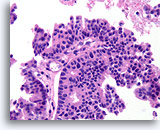

Papilloom, Borst FNA, Celblok.

Deze afbeelding van dezelfde FNA als in afbeelding 18 bevat een duidelijk papillaire architectuur.

10X

Papilloom, Borst FNA, Celblok.

Deze afbeelding van dezelfde FNA als in afbeelding 18 bevat een duidelijk papillaire architectuur.

10X

Papilloom, Borst FNA, Celblok.

Met een sterkere vergroting kan een gemengde celpopulatie gezien worden die het oppervlak en de onderliggende melkgangen bekleden. Een rij myoepitheliale cellen is zichtbaar tussen de ductale cellen en het onderliggende stroma (pijl). Let op de spleetachtige ruimte die kenmerkend is voor typische hyperplasie (open pijl).

40X

Papilloom, Borst FNA, Celblok.

Met een sterkere vergroting kan een gemengde celpopulatie gezien worden die het oppervlak en de onderliggende melkgangen bekleden. Een rij myoepitheliale cellen is zichtbaar tussen de ductale cellen en het onderliggende stroma (pijl). Let op de spleetachtige ruimte die kenmerkend is voor typische hyperplasie (open pijl).

40X